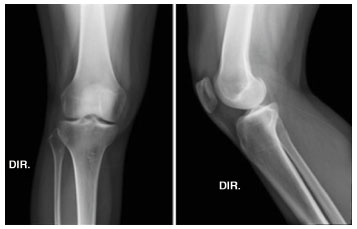

Foi submetida a exames laboratoriais, radiografia do joelho direito e ressonância nuclear magnética (RNM) no joelho e ombro direito. A radiografia apontou apagamento do coxim gorduroso suprapatelar, sugerindo reação sinovial (Figura 1). A RNM do joelho apontou acentuado derrame articular, pelo que, foi realizada punção do líquido articular (Figura 2). A análise do líquido apresentou 2.240 leucócitos por mm3, com 1.366 polimorfonucleares por mm3. As culturas e a bacterioscopia foram negativas. A RNM do ombro apontou derrame articular acromioclavicular e glenoumeral.